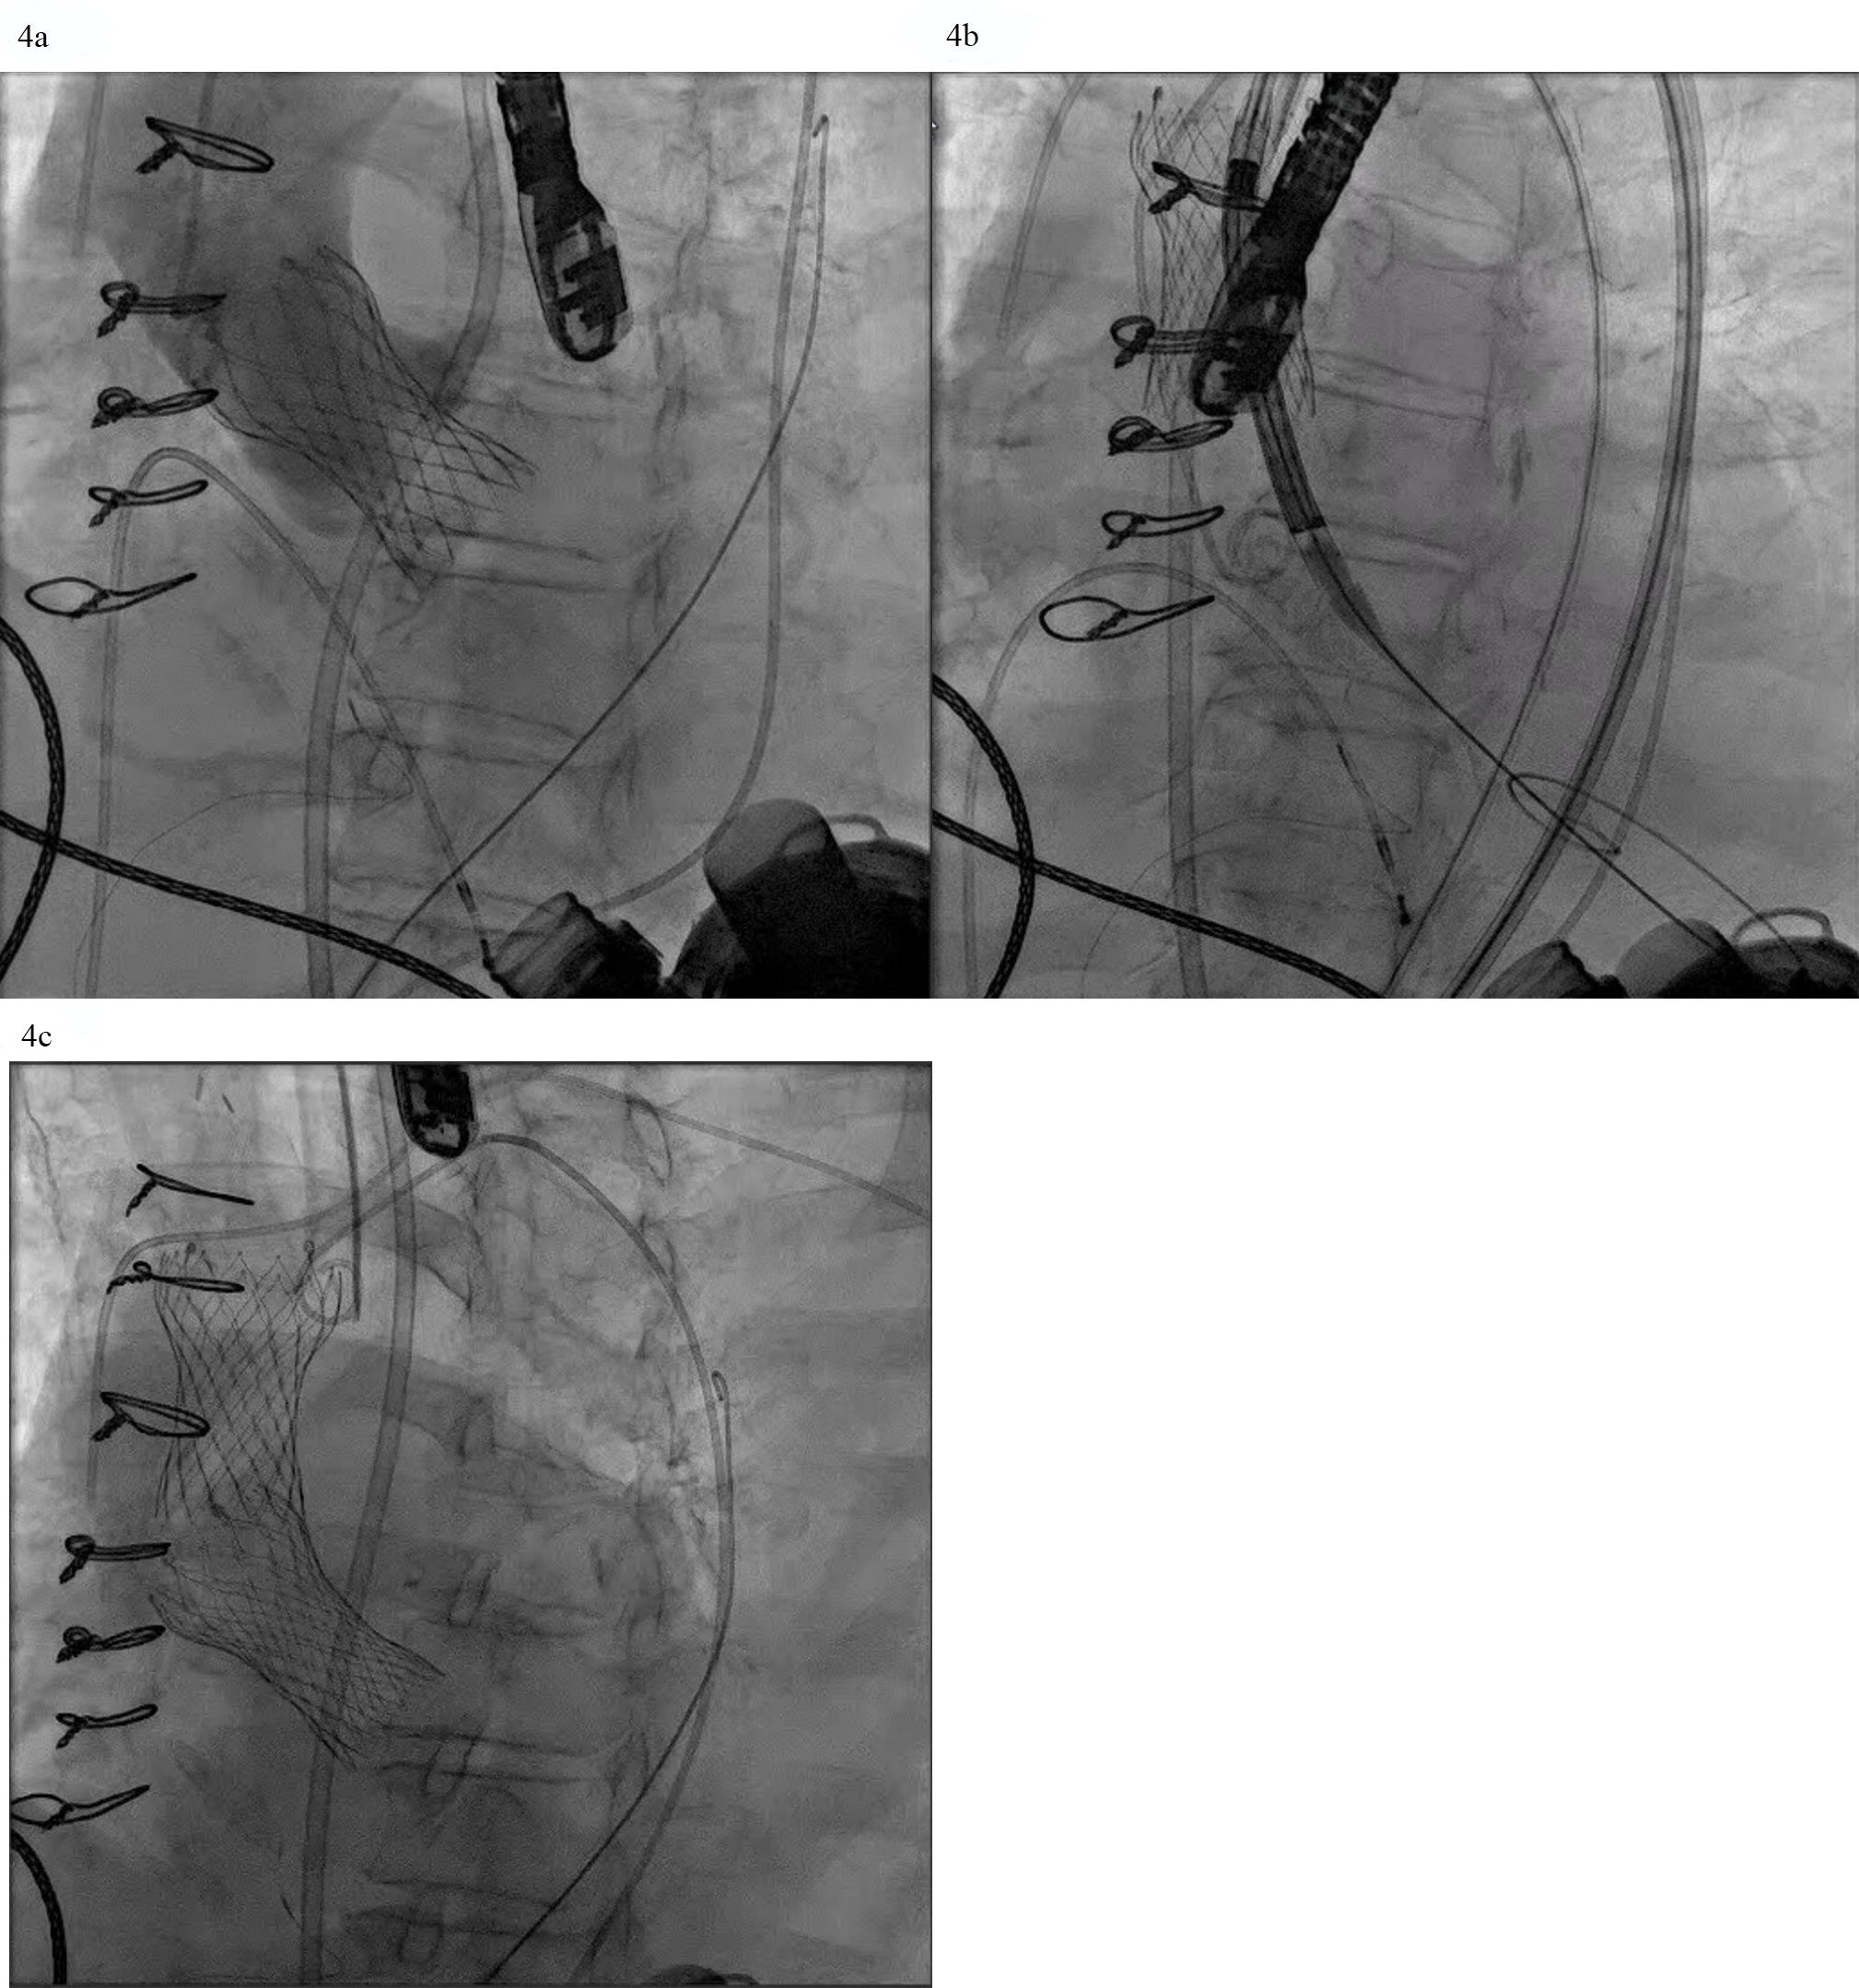

TAVR for AR in patients with LVADs poses additional challenges. The continuous pressure head in the aortic root from LVAD outflow cannula flow increases the risk of ventricular migration. If perivalvular regurgitation is present again the magnitude is magnified by the constant Ao-LV pressure gradient (Fig. 2). The absence of leaflet calcification leads to an increased risk of device misplacement or migration and paravalvular regurgitation from an incomplete seal (Fig. 4a,b). A valve-in-valve strategy in which a second valve is delivered to hold the first valve in place and prevent its migration has been deployed successfully (Fig. 4c). To minimize this risk, LVAD flows should be temporarily decreased during valve deployment. A single center experience which utilized predominantly the self-expanding Evolut TAVR platform reported that 36% of the procedures required a second valve [17]. The French registry of TAVR for native aortic regurgitation noted an 8.8% rate of second valve implantation that portends a worse clinical outcome [18].

Fig. 4. AVR with a self-expanding valve (Medtronic) in LVAD complicated by migration. (a) Medtronic Evolut valve deployed too deep in the ventricle. (b) Evolut valve embolized to the aorta when attempting to reposition the valve with a snare. (c) Second Evolut valve successfully placed across the aortic valve.